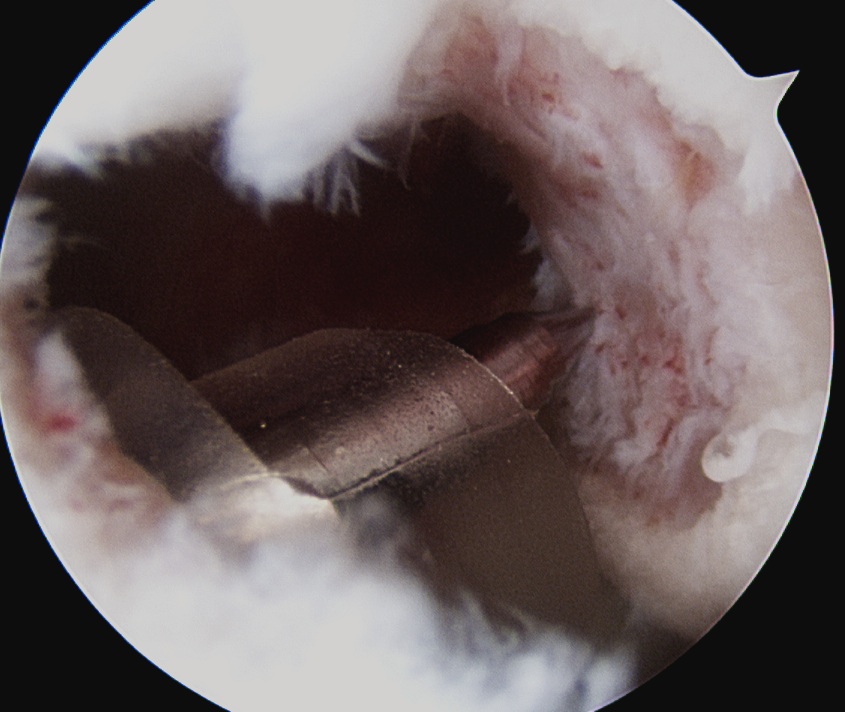

- insert anchors at medial aspect of defect

Anchor insertion into Hill Sachs lesion